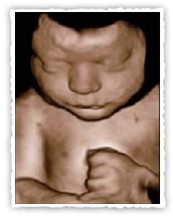

In der Frühschwangerschaft (13-17. Schwangerschaftswoche) lassen sich

Bewegungsabläufe und das Kind noch als Ganzes darstellen.

Aufnahme in der 23. Schwangerschaftswoche (links)/ 32. Schwangerschaftswoche (rechts)